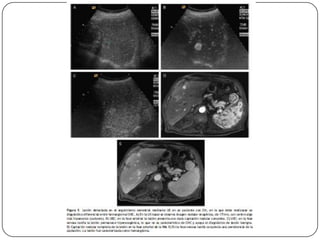

Auxiliares de diagnóstico

 RM

 No utiliza contraste intravenoso

 Es más eficaz que la TC para diferenciar el CH de

nódulos de regeneración

 TAC

 Sensibilidad del 68% con especificidad de 93%, se

utiliza para precisar las alteraciones vistas en el

usg.